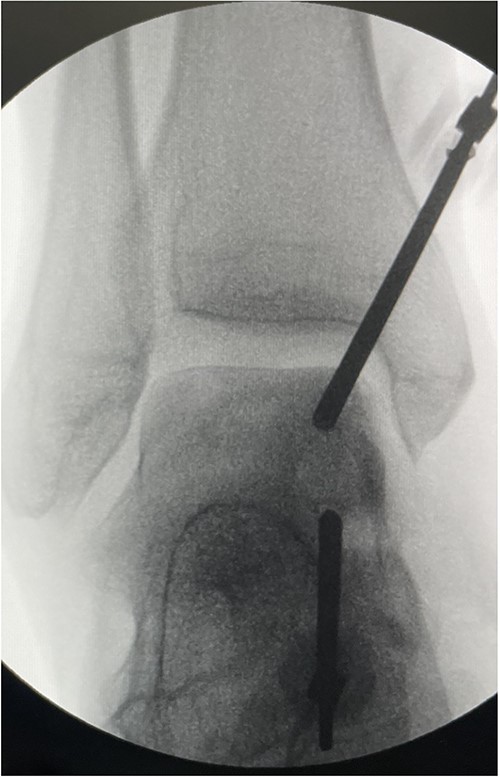

To address the subchondral cyst, we performed an arthroscopic subchondroplasty using calcium phosphate paste. A full-thickness articular cartilage loss corresponded to the subchondral cyst at the medial talar dome. The subchondral cyst was identified under fluoroscopy, and a trocar was inserted into the cyst under X-ray guidance. Next, 3 cc of calcium phosphate paste was injected into the cyst guided by fluoroscopy to obtain satisfactory filling and ensuring no leakage into the joint space (Fig. 2). This was a day case procedure, and the patient returned home the same day.